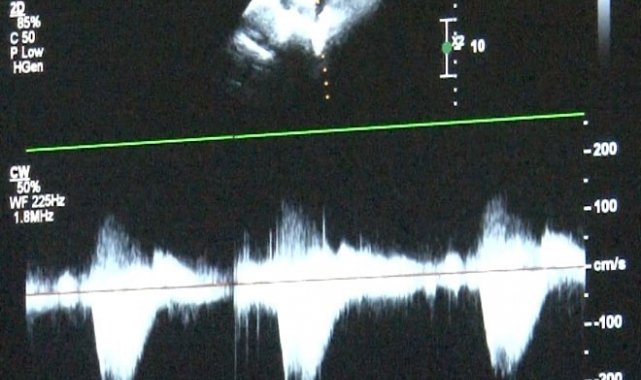

'Sağlık Bakanlığı verilerine göre her yıl bin canlı doğumdan 8'inde doğumsal kalp hastalığı görebilmekteyiz' diyerek sözlerine başlayan Uzm. Dr. Damla Gökçeer Akbulut, "Yılda 12 bin çocuk doğumsal kalp hastalığıyla dünyaya geliyor. Çeşitli nedenleri olabiliyor bazen annenin gebelikte kullandığı ilaçlar ya da diyabet gibi bir hastalığı olması, genetik rahatsızlıklar, bunlar genetik olarak kalp rahatsızlıklarına yol açabiliyor. Bu hastalarda erken tanı mümkün, daha anne karnındayken fetal ekokardiyografi (anne karnındaki bebeğin kalp yapısını ve işlevini değerlendirmek amacıyla kullanılan bir tıbbi görüntüleme)yle doğumsal kalp hastalığı olan bebeklerde doğum sonrası erken müdahale yapabiliyoruz. Bazı bebekler mor doğabiliyor ancak bazılarında bu bulgular ilk ay içinde gelişebiliyor" dedi.